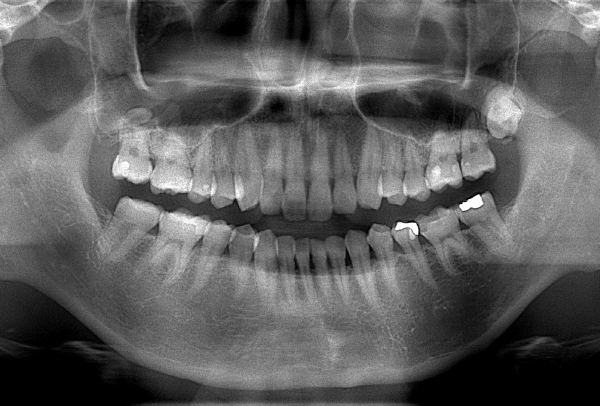

インレー症例

初診時パノラマ

初診時口腔内写真

iTero NIRI機能による診査

虫歯除去後

初診時バイトウィングデンタル

レントゲンだとちょっと虫歯が怪しいくらいに写っている。これだけだと確定診断としては、判断材料が少ないと考えられる。

黄色丸の部位が、他の部位と違って白く抜けがあるのがわかります。これがNIRI機能による虫歯の診査です。

この機能のおかげで、歯と歯の間の見つけにくい虫歯がよくわかるようになってきました。

In(インレー)セット後

当院では自費のインレー(つめ物)の場合、ゴムのシートをかけてから詰めていきます。

ゴムのシートをすることで、歯面を最大限乾燥することができ、接着力が上がる他、操作時の材料の誤飲の防止、接着剤の歯肉縁下(歯ぐきの中)への侵入を防止するなどといったメリットがあります。(歯の並びによっては、ゴムのシートができないことがあります。また、シートをかけることで苦しくなる、苦手という方には無理に行いません。)

年齢・性別 40代・男性

主訴 左上の奥歯がしみることがある

治療内容 左上4の虫歯

治療期間 2週間

リスク・副作用 虫歯の大きさによっては、神経をとらないといけなくなることがあります。

また、虫歯が大きかったケースで神経を残した場合、治療後にしみるなどの

症状が続くことがあります。

費用 ・ジルコニアインレーで修復

55,000円

治療方針

IOSのNIRI機能によって虫歯部分が明らかになったので、虫歯を除去後に修復治療を行うこととしました。

特記事項

ラバーダムは歯とつめ物をくっつける際に非常に効果的です。

人間は呼吸をしますので、お口の中はかなり湿度が高くなっています。水が多い状態でものをくっつけようと思ってもなかなかくっつかないということと同じになります。

ですので、呼気中の湿度に左右されないようにするために、ラバーダムを用いて接着力を高くしています。

ラバーダムで息が苦しくなる場合は使用しませんし、ラバーのアレルギーがある場合も使用できません。

担当医師所見

虫歯の有無を確認する上で今まではレントゲンと自分の目での確認でした。現在は目で見るよりもはるかにわかりやすいIOSという装置がありますので、虫歯の発見がしやすくなりました。

そのため、患者さんの虫歯の進行の段階が早いうちにわかる様になり、神経をとらなければならないというケースが非常に少なくなっています。